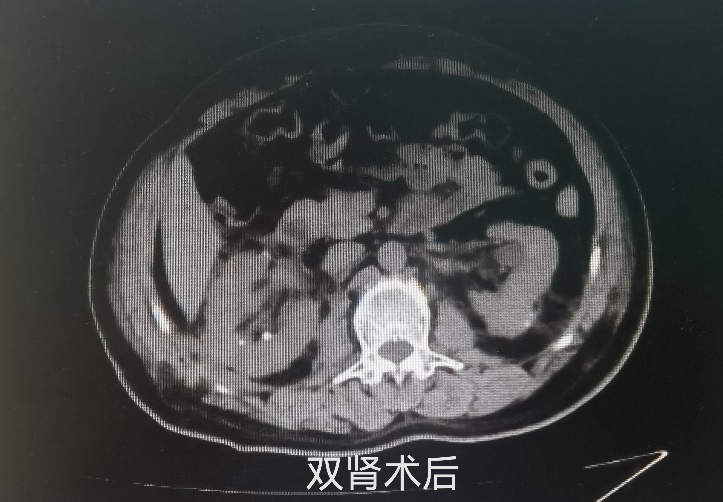

最终,通过泌尿外科团队、手术室麻醉科及护理团队的密切配合,李大爷的手术获得了成功,为他保住了肾脏。术后复查肾功能血肌酐虽然有一过性的轻度升高,但是在3天之后恢复正常,未出现肾功能不全。

救死扶伤显大爱,医患和谐暖人心。春节前夕,李大爷顺利康复出院,临行前一家人满怀感激的与泌尿外科的医护人员一一告别,感谢吉林省肿瘤医院给了他“第二次生命”。